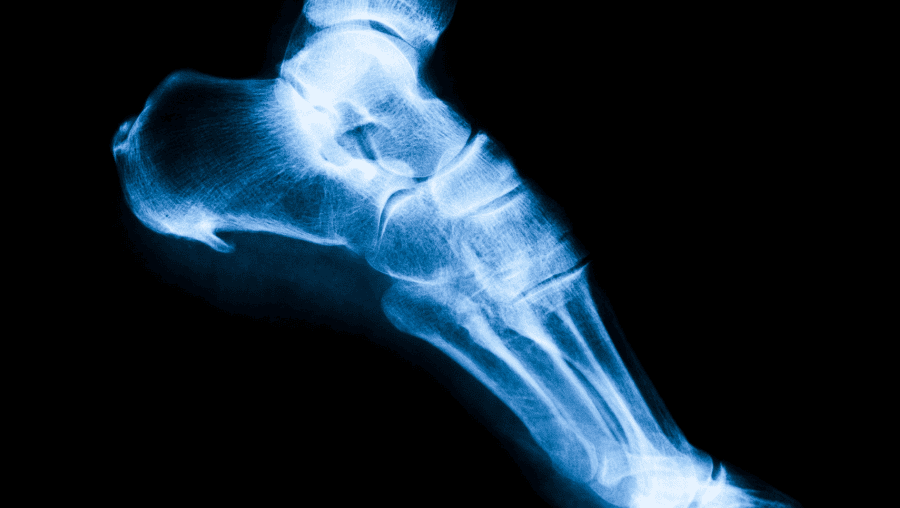

骨刺

骨刺,也稱為骨質增生或骨刺,是一種骨頭增生的情況,通常與關節炎或其他關節問題相關。對於骨刺的復健和伸展指南,目標是緩解疼痛、增加關節靈活性,並減少症狀對日常生活造成的影響。以下是一些可能有助於骨刺的復健和伸展的養生建議: